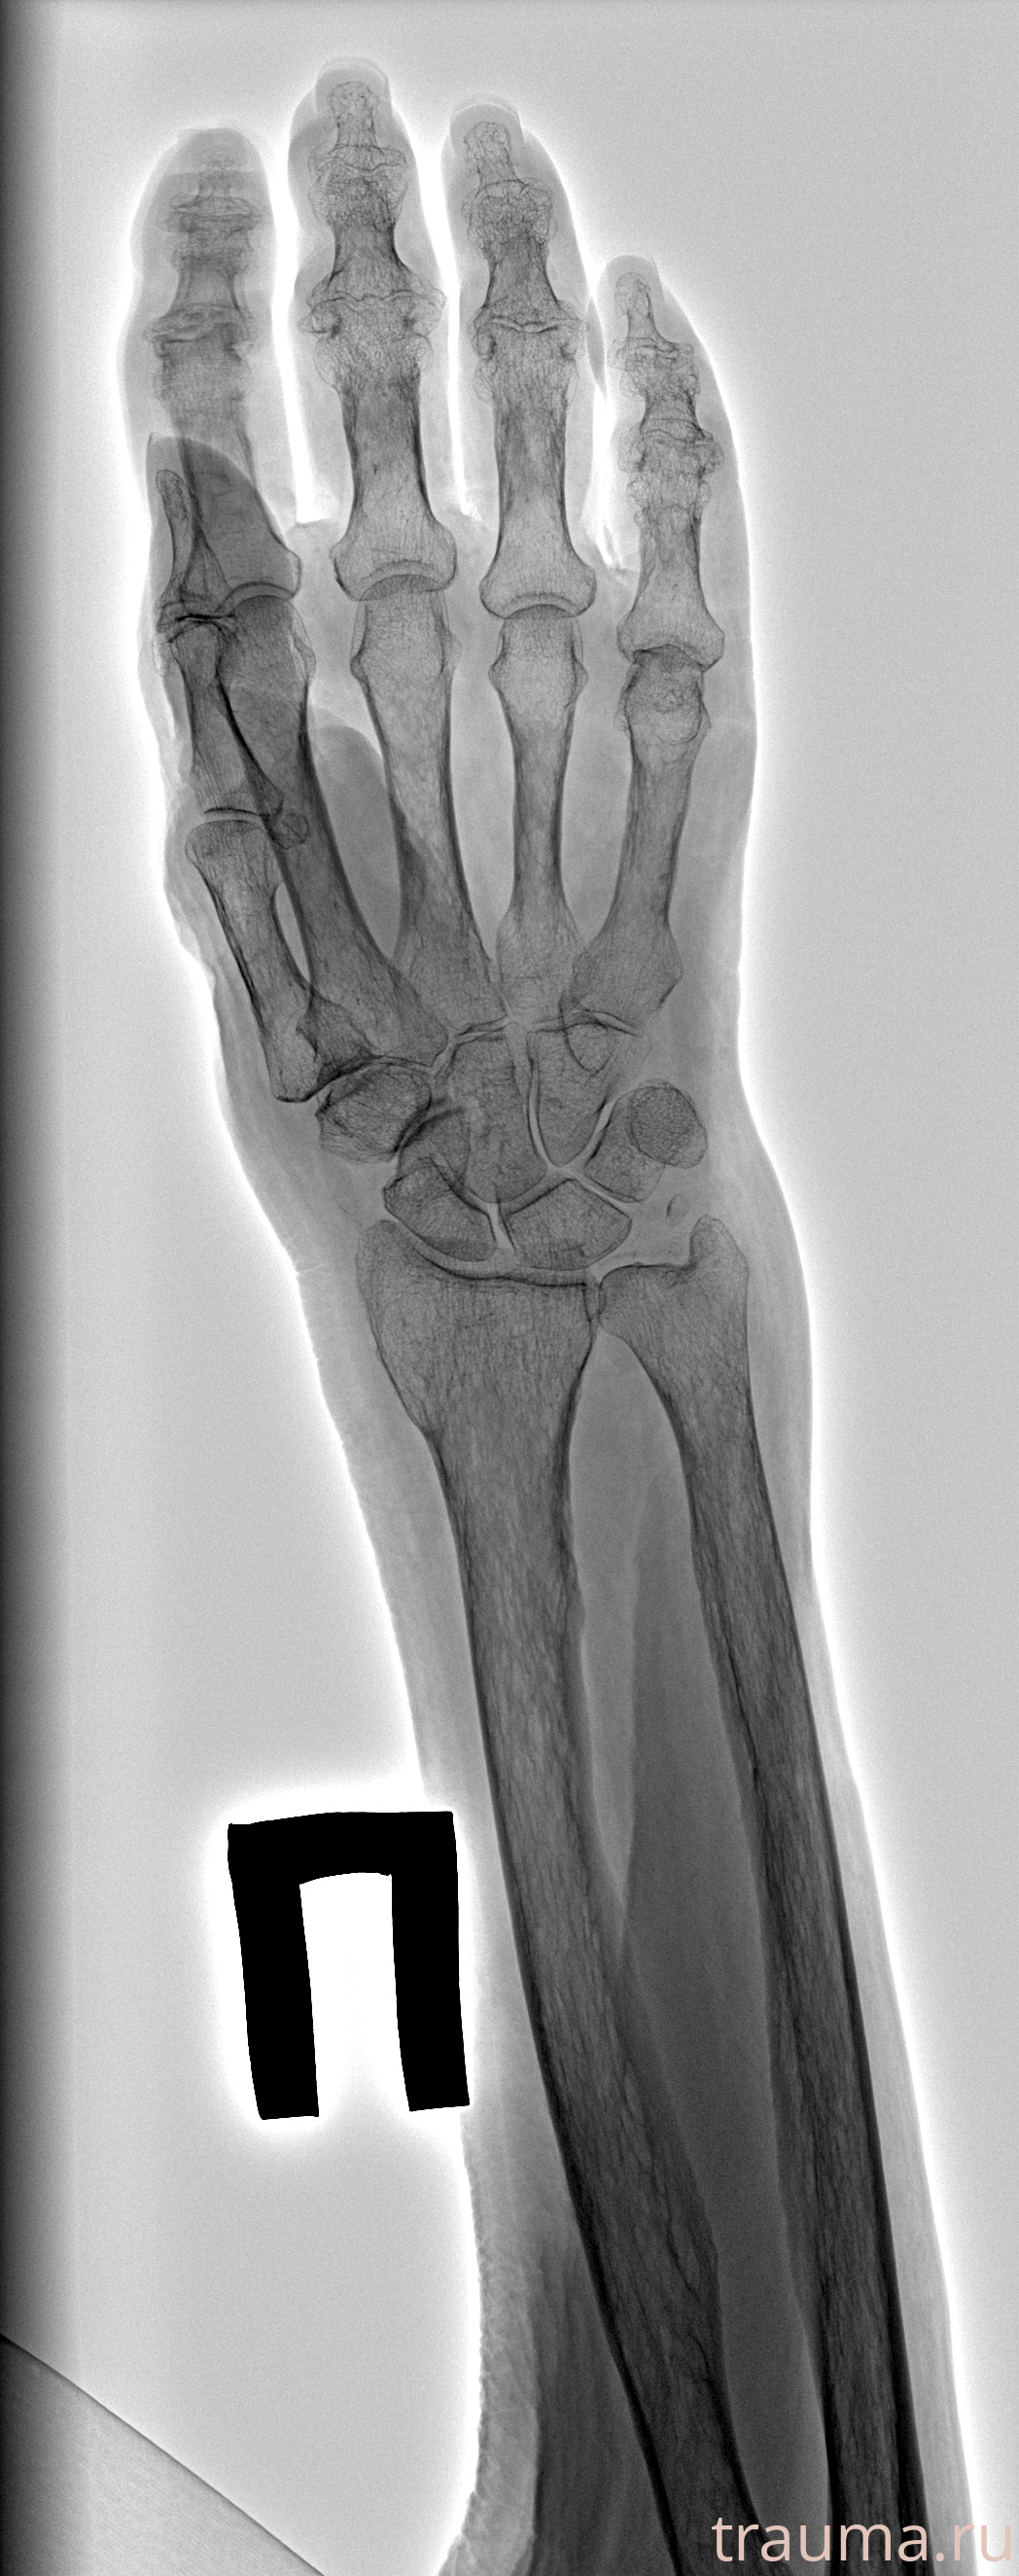

Рентген на дому: по вашему адресу приезжает врач-рентгенолог, травматолог-ортопед с мобильным рентгеновским аппаратом, проводит диагностику травмы или заболевания, делает необходимые рентгенограммы, дает рекомендации по дальнейшему лечению. Получить качественные снимки в домашних условиях возможно благодаря уникальной методике, разработанной МосРентген Центром для института  Склифосовского